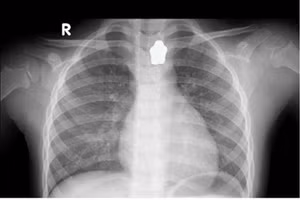

GD&TĐ - Nuốt 20 viên bi nam châm, bệnh nhi 4 tuổi bị dính 5 quai ruột với nhau, thủng 8 vị trí, phải phẫu thuật cắt bỏ 15cm ruột.